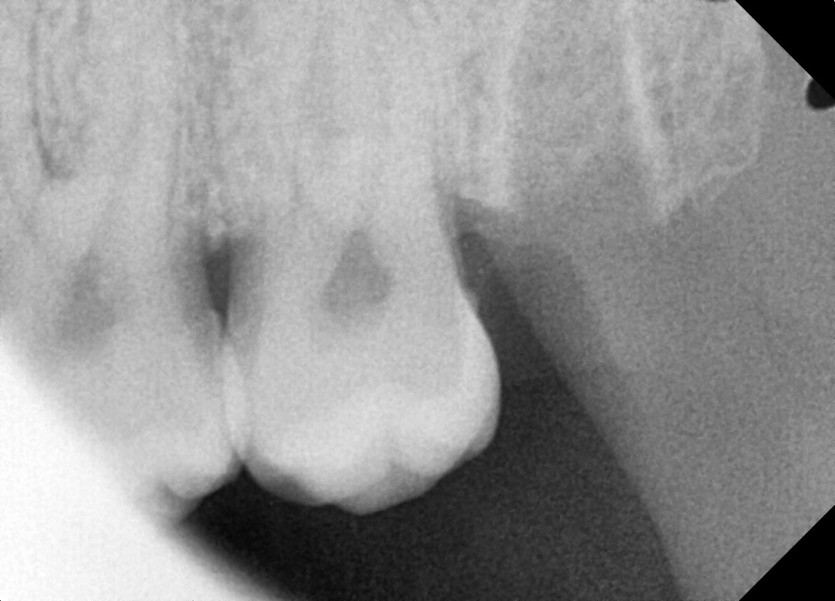

#28,38 사랑니 발치

구강 외과 전문의가 당일 발치했습니다.